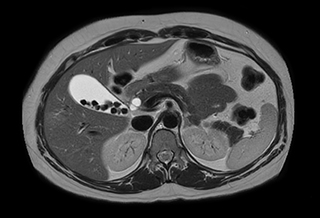

Ascites can be hard to image, but excellent result is obtained with Ingenia Ambition. This high resolution image demonstrates the high quality that can be obtained with VitalEye and the patient just breathing normally. The acquisition time is fast thanks to the accuracy of the respiratory gating with VitalEye** and it also saves the time needed to put a respiratory belt on the patient.

3D T2 with VitalEye